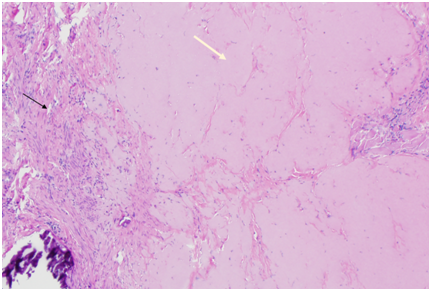

The CSD resection specimen collected intraoperatively was sent for pathologic examination and showed hyalinized and fibrotic tissue with chronic inflammation, consistent with old cesarean scar (Figure 3).

Figure 3 Patient 1, Pathology: Hyalinized cesarean scar (white arrow) and background uterine myometrium (black arrow). (H&E stain).

The CSD resection specimen was sent for pathologic examination which showed fragments of endomyometrial tissue with scarring consistent with the cesarean scar, along with old placental side nodule with dystrophic calcifications (Figure 6) (Figure 7).

Figure 7 Patient 2, Pathology slides: a. The pathology figure 7a would roughly correspond to the red circle in figure 6: Low power view of resected fibrotic cesarean scar (white arrow) with placental site nodule (black arrow). (H&E stain) b. High Power view of placental site nodule (black arrow) showing hyalinization with degenerative implantation site trophoblast. (H&E stain).